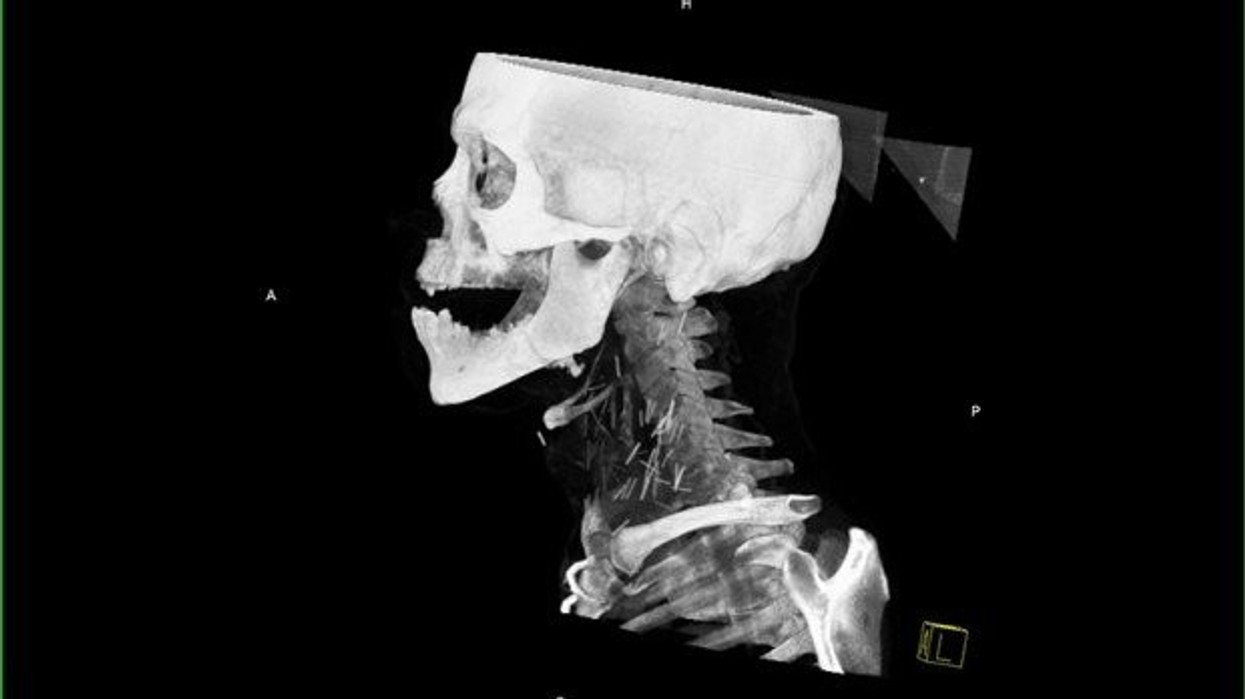

Pacienti i cili për një kohë të gjatë kishte qenë i varur nga heroina ka bërë një fotografim me rreze x, i cili ka zbuluar një të vërtetë të tmerrshme.

Fotografia e rëntgenit me rreze x ka nxjerr në pah dhjetëra gjilpëra të thyera në qafën e tij, ndërsa pas rekonstruimit të fotografisë në versionin 3D nga radiologët, është konstatuar se vërtetë bëhet fjalë për dhjetëra gjilpëra.